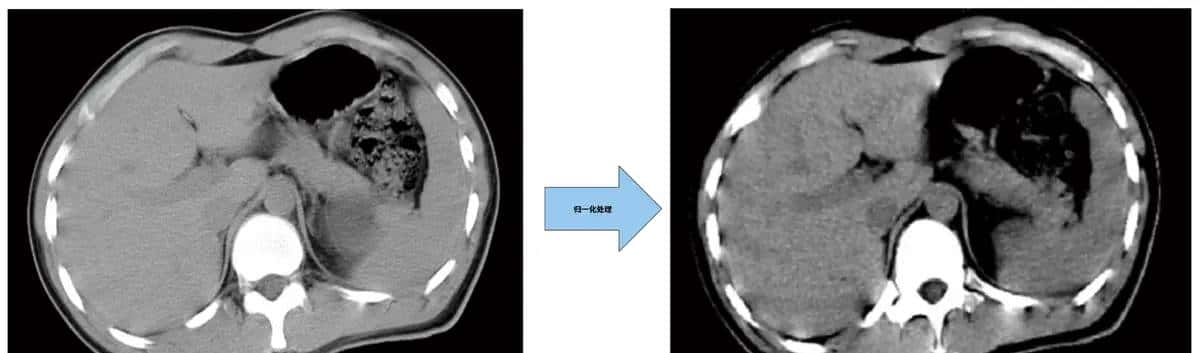

5.图像归一化

图像归一化是指对图像进行了一系列标准的处理变换,使之变换为一固定标准形式的过程。归一化思想是通过数学手段,把不明显的像素、过亮、过暗的像素进行必定程度的屏蔽,突出有价值的像素,以加快训练网络的收敛性、简化计算。在案例中主要通过归一化去减小医学图片,也可以必定程度消除由于光线不均匀而造成的干扰。案例中将每个像素的像素值直接除以图片最高像素值255,而后对标签数据进行灰度处理,数值大于0.5的赋为1,小于等于0.5则赋为0,使得原照片像素值从0-255变成了0-1,在实际应用时需根据自己的样本照片像素值特征设计特有的归一化算法。

这样处理后的图片中线条的变得更清晰,由于线条边缘的灰度像素被强制设定为0(白色)或者1(黑色),当然实践时也可以通过一些算法把过暗、过亮的像素进行归一化处理:

虽然归一化处理可以降低图片中数据的复杂度,但是也会导致必定程度的失真,当然也有其他手段避免这一问题,同样也会增加复杂度和计算成本。